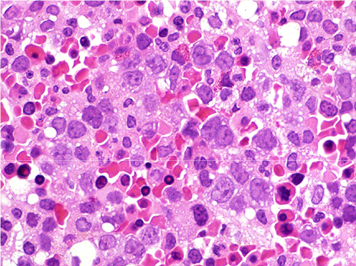

図は巨赤芽球性貧血の骨髄組織である.原因について正しいのはどれか.

日本病理学会「病理コア画像」よりhttp://jsp.umin.ac.jp/corepictures2010/01/c02/01.html

・megaloblastic (macrocytic) anemia巨赤芽球性貧血

・hypersegmented neutrophils (> 5 lobes)好中球の過分葉

・hypersegmented neutrophils好中球の過分葉

正解:e.h